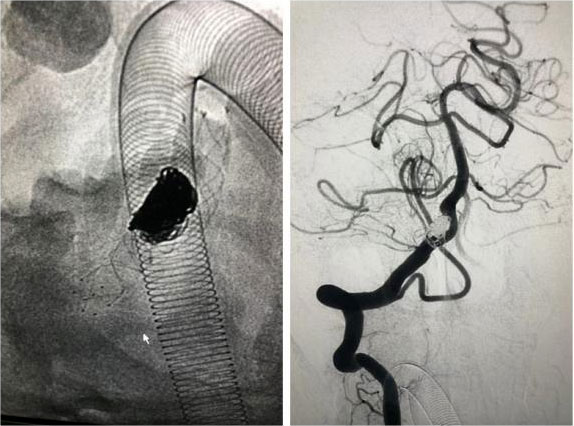

动脉瘤栓塞术:

只需要在病人大腿根部开个小切口,用一根纤细的微导管经血管抵达所要治疗的动脉瘤部位,向动脉瘤内堵塞非常精细的弹簧圈,达到很好治疗动脉瘤的目的。是微创外科的方法之一。

▲ 一位动脉瘤患者术前影像

▲ 术后,造影显示动脉瘤无显影,栓塞成功